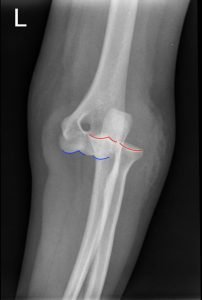

Posterior Elbow Dislocation, Oblique XRay, dislocated, Annotated. JETem 2016